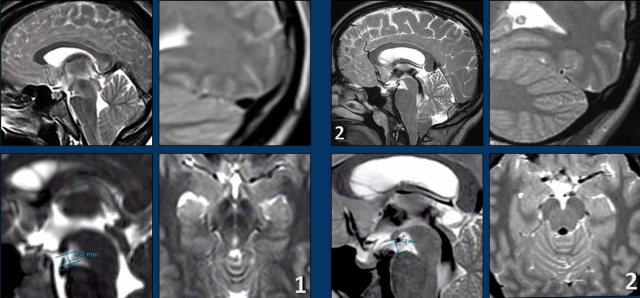

Although SIH and Chiari malformation type I (CM1) are very different conditions, they both can present with chronic headaches and low-lying cerebellar tonsils.

In patients with SIH this can lead to a misdiagnosis of a CM1.

Both patients are young women with chronic headaches.

Which one has SIH and which one has CM1?

- Low-lying cerebellar tonsils

It is not very obvious also due to some movement artefacts, but the shape of the brainstem is not normal and there seems to be a short distance between the pons and the mamillary bodies.

Maybe there is also some venous congestion. - Besides low-lying cerebellar tonsils, the image looks normal.

Images

- The four images on the left show the typical findings of SIH with a convex border of the transverse sinus, a short distance between the mamillary bodies and the pons and midbrain sagging.

- The images on the right do not show these findings.

The patient with SIH was treated four times with a blind blood patch, which was succesful.

The patient with the Chiari type 1 had a craniocervical decompression with a good result.

It is our duty as radiologist to save patients with SIH from being treated as Chiari 1 patients.